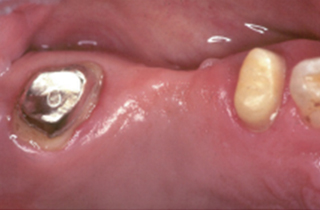

치아의 길이가 너무 짧은 경우는 치아의 길이를 늘리는 수술이 필요하기도 합니다.